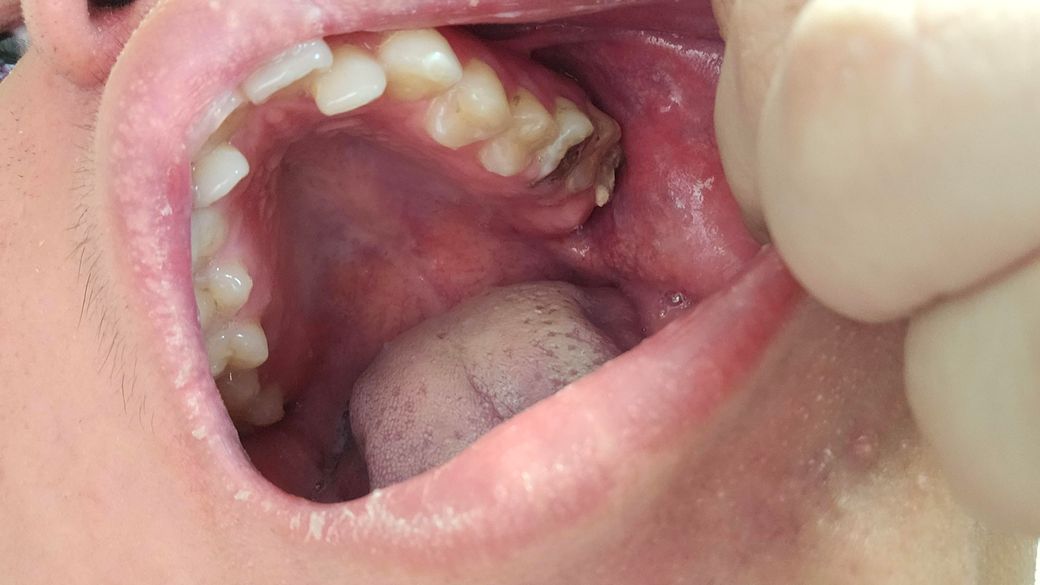

치과 갔면 무슨 치료 가능하가?아니면 발치하는가

제가 11월2일 치과 갔는데요 조금 늦게 갔는것가요? 제가 이사진찍히이빨상태 이렇게되는데요 다음주 토요일 갔도 치료할수있나요 알려주세요

치아의 상태가 안좋기 때문에 임플란트를 해야할 가능성이 높아보이고 종합적인 치료가 필요해보입니다.

사진상으로는 아래치아는 발치를 해야될것같고, 위쪽치아는 엑스레이 사진을 찍고 나서 치료 방법을 선택해야될것같습니다.

사진으로 봤을 경우에는 충치가 매우 많이 진행된 것으로 보입니다. 충치가 치아 뿌리까지 진행되었다면 치아를 발치하고 임플란트 치료 등이 필요할 수 있습니다. 자세한 확인을 위해서 치과에서 진료를 받아보는 것을 권유 드립니다.

치아 충치가 아주 깊습니다. 엑스레이 찍어보고 좀 더 검사를 해봐야겠으나 치료가 가능하다면 신경치료하고 씌우는 치료이나 발치 가능성이 높을 것 같습니다. 발치 가능합니다. 마취합니다.